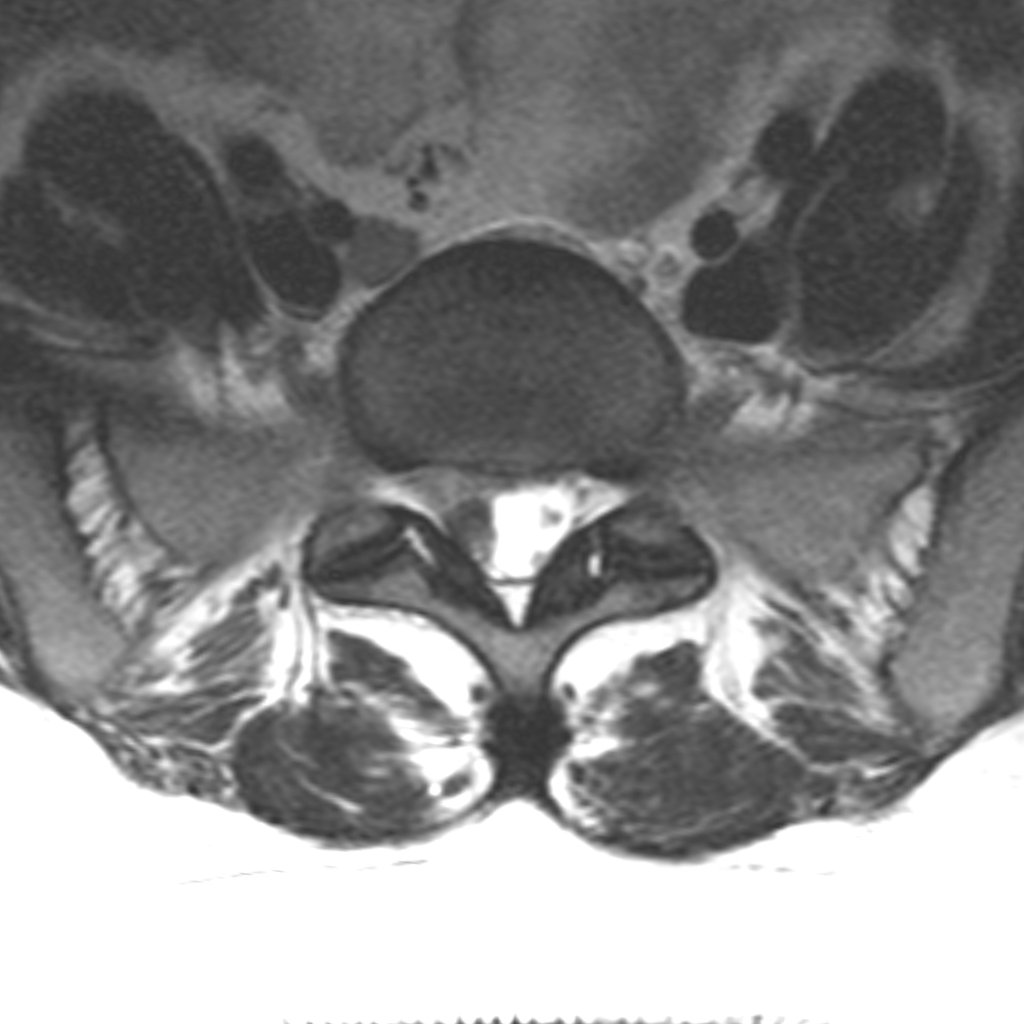

Axiális MRI felvétel — lumbális porckorongsérv

MRI: lumbális porckorongsérv — a porckoronganyag az ideggyökre nyomást gyakorol